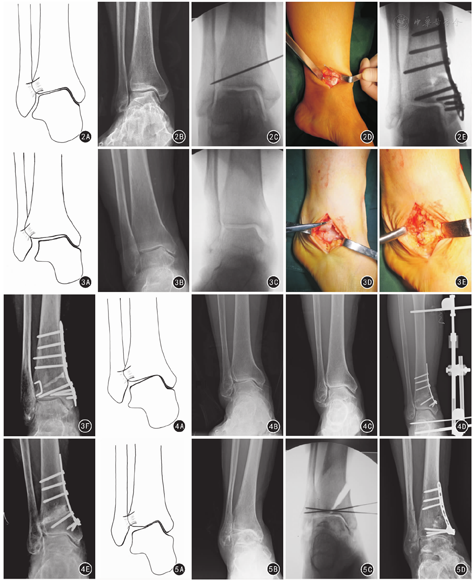

临床评估内容包括术后骨性愈合情况、手术并发症、术前及末次随访的美国足踝骨科协会(American Orthopedic Foot and Ankle Society, AOFAS)踝与后足评分和踝关节骨关节炎量表(Ankle Osteoarthritis Scale, AOS)疼痛、功能评分[17]。将改良Takakura分期的2、3A、3B及4期分别赋值为2、3、4、5,便于统计后进行术前与术后计量资料比较。在踝关节正侧位X线片上,分别测量患者手术前后胫骨前侧关节面角(tibial anterior surface angle, TAS),即胫骨轴线与胫骨远端关节面的夹角;距骨倾斜角(talar tilt angle, TT),即胫骨远端关节面与距骨穹隆关节面的夹角;胫骨踝穴角(tibiocrural angle, TC),即胫骨轴线与内外踝尖连线的夹角;胫骨内踝角(tibial medial malleolus angle, TMM),即胫骨轴线与内踝关节面的夹角,以及胫骨侧位关节面角(tibial lateral surface angle, TLS),即踝关节侧位X线片上胫骨轴线与胫骨远端关节面的夹角。见图1。所有影像学测量由2名主治医师独立完成,测量结果有差异时,由第三名副主任医师评判取值。

注:TAS为胫骨前侧关节面角,即前后位X线片上胫骨轴线与胫骨远端关节面的夹角;TT为距骨倾斜角,即前后位X线片上胫骨远端关节面与距骨穹隆关节面的夹角;TC为胫骨踝穴角,即前后位X线片上胫骨轴线与内外踝尖连线的夹角;TMM为胫骨踝穴角,即前后位X线片上胫骨轴线与内踝关节面的夹角;TLS为胫骨侧位关节面角,即侧位X线片上胫骨轴线与胫骨远端关节面的夹角